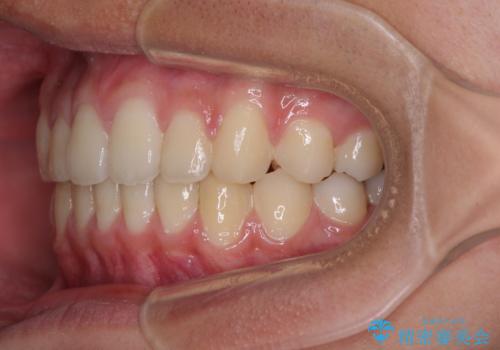

- 前歯のデコボコと隙間を気にして来院された高校生の患者様です。

下顎前歯が上顎前歯を突き上げるような咬み合わせとなっており、その影響で上顎正中に隙間ができている状態でした。

叢生の程度は軽度であり、本人もしっかりと使用する自信があるとのことだったので、インビザラインによる矯正治療を行うこととしました。

突き上げによる隙間を予防する為に、深い咬み合わせを改善するような治療計画としました。咬み合わせを改善させることはできましたが、隙間は後戻りしやすいので、通常の下顎前歯のみではなく、上顎前歯2本もワイヤーで保定を行いました。